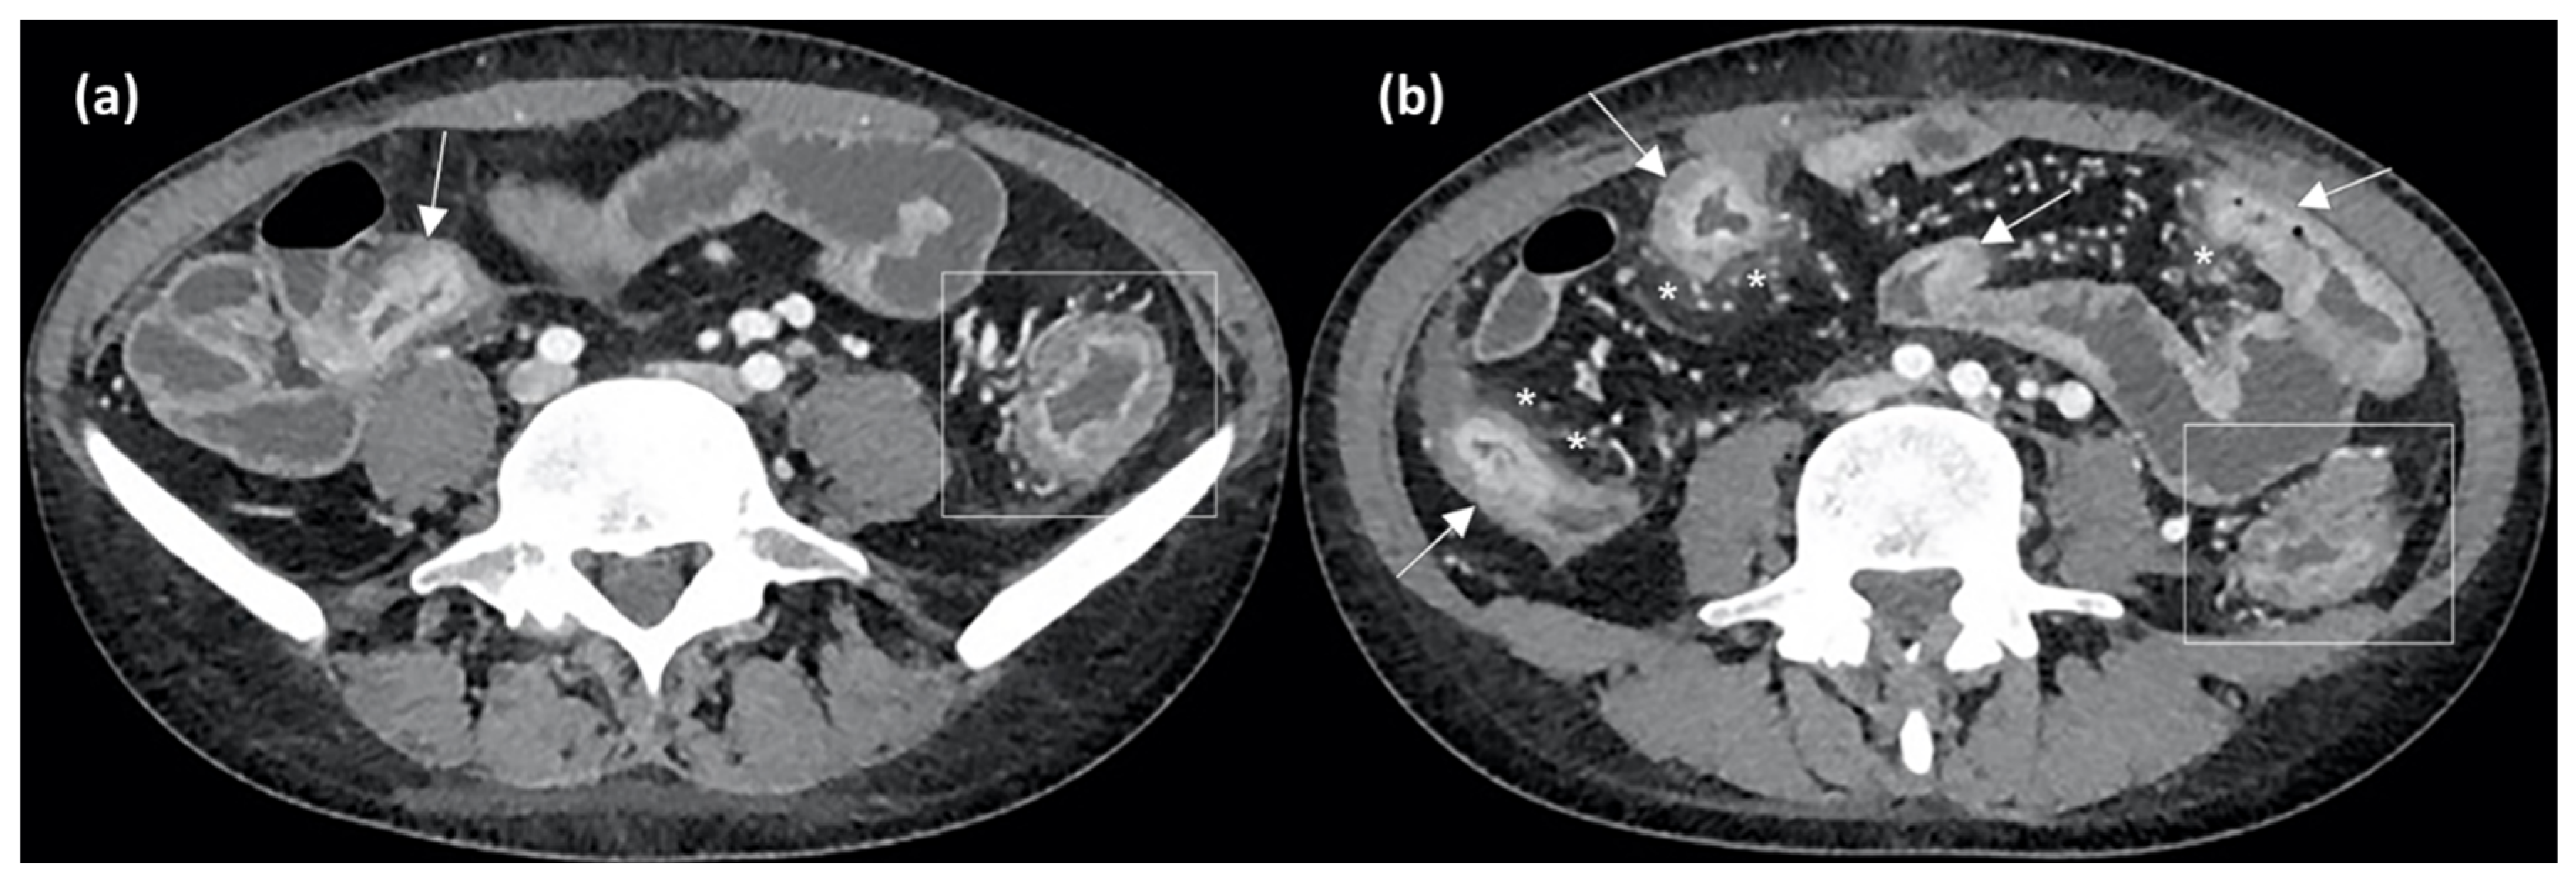

- Horsthuis, K.; Bipat, S.; Bennink, R.J.; Stoker, J. Inflammatory bowel disease diagnosed with US, MR, scintigraphy, and CT: Meta-analysis of prospective studies. Radiology 2008, 247, 64–79. [Google Scholar] [CrossRef] [PubMed]

- Wang, Y.; Zhang, R.-N.; Mao, R.; Li, X.-H. Inflammatory bowel disease cross-sectional imaging: What’s new? United Eur. Gastroenterol. J. 2022, 10, 1179–1193. [Google Scholar] [CrossRef]

- Alyami, A.S. The Role of Radiomics in Fibrosis Crohn’s Disease: A Review. Diagn. Basel Switz. 2023, 13, 1623. [Google Scholar] [CrossRef]

- Meng, J.; Luo, Z.; Chen, Z.; Zhou, J.; Chen, Z.; Lu, B.; Zhang, M.; Wang, Y.; Yuan, C.; Shen, X.; et al. Intestinal fibrosis classification in patients with Crohn’s disease using CT enterography-based deep learning: Comparisons with radiomics and radiologists. Eur. Radiol. 2022, 32, 8692–8705. [Google Scholar] [CrossRef]

- Li, X.; Liang, D.; Meng, J.; Zhou, J.; Chen, Z.; Huang, S.; Lu, B.; Qiu, Y.; Baker, M.E.; Ye, Z.; et al. Development and Validation of a Novel Computed-Tomography Enterography Radiomic Approach for Characterization of Intestinal Fibrosis in Crohn’s Disease. Gastroenterology 2021, 160, 2303–2316.e11. [Google Scholar] [CrossRef]

- Laterza, L.; Boldrini, L.; Tran, H.E.; Votta, C.; Larosa, L.; Minordi, L.M.; Maresca, R.; Pugliese, D.; Zocco, M.A.; Ainora, M.E.; et al. Radiomics could predict surgery at 10 years in Crohn’s disease. Dig. Liver Dis 2022, 55, 1042–1048. [Google Scholar] [CrossRef] [PubMed]

- Chen, Y.; Li, H.; Feng, J.; Suo, S.; Feng, Q.; Shen, J. A Novel Radiomics Nomogram for the Prediction of Secondary Loss of Response to Infliximab in Crohn’s Disease. J. Inflamm. Res. 2021, 14, 2731–2740. [Google Scholar] [CrossRef] [PubMed]

- Zhu, C.; Hu, J.; Wang, X.; Li, C.; Gao, Y.; Li, J.; Ge, Y.; Wu, X. A novel clinical radiomics nomogram at baseline to predict mucosal healing in Crohn’s disease patients treated with infliximab. Eur. Radiol. 2022, 32, 6628–6636. [Google Scholar] [CrossRef] [PubMed]